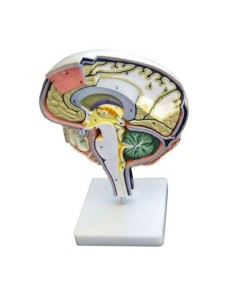

Dal cranio in 22 parti con incastri magnetici ai modelli di colonna vertebrale, da quelli di articolazioni a quelli di cuore, ogni pezzo della nostra collezione è progettato per un’immersione totale nello studio dell’anatomia umana. I nostri modelli, realizzati tramite scansioni di ossa vere, garantiscono un’esperienza tattile autentica e una fedeltà di peso quasi identica agli originali.

Essenziali per studenti e professionisti, i nostri modelli anatomici sono strumenti didattici che permettono di osservare le strutture anatomiche con precisione, eliminando la necessità di dissezioni o studi invasivi. Sono inoltre utili per spiegare ai pazienti le patologie, rendendo la comunicazione più efficace e risparmiando tempo prezioso.